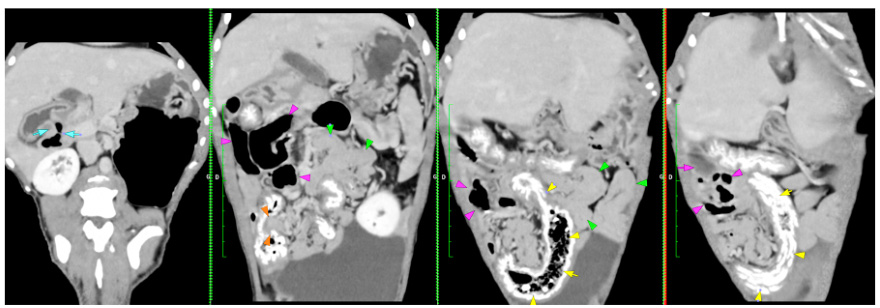

<div class="et_pb_text_inner"><p>No wonder he was so uncomfortable. We suspected that Rex had landed on the stick with force and as the stick was wet and rotten it had snapped. This left us with other worries how far had the stick gone, what actual damage had it done and were there any other bits of stick present. Any little splinters could cause future problems. Thankfully after flushing the wound continuously for several minutes we able to perform a <a href="https://mochdrevets.co.uk/ct-scanner/" target="_blank" rel="noopener">CT scan</a>. The results were excellent and exactly what we hoped for. We were able to rule out any damage or any lingering pieces.</p></div>

<p>And in case you want to know what the specialist saw on the CT?</p>

<p>There is a poorly defined region of hypo attenuation and focal swelling within the root of the tongue on midline (Figure 1, red arrowheads). Numerous small gas foci are present within the tongue and geniohyoid/mylohyoid muscles with subjective enlargement and presumed contrast enhancement of rostral aspect of the layer. There is fluid accumulation in the le retropharyngeal space and overlying subcutaneous space (Figure 2, green arrowheads). Rostrally, numerous small gas foci are seen between the le aspect of the tongue and digastricus muscle (Figure 3, yellow arrowheads)</p></div>